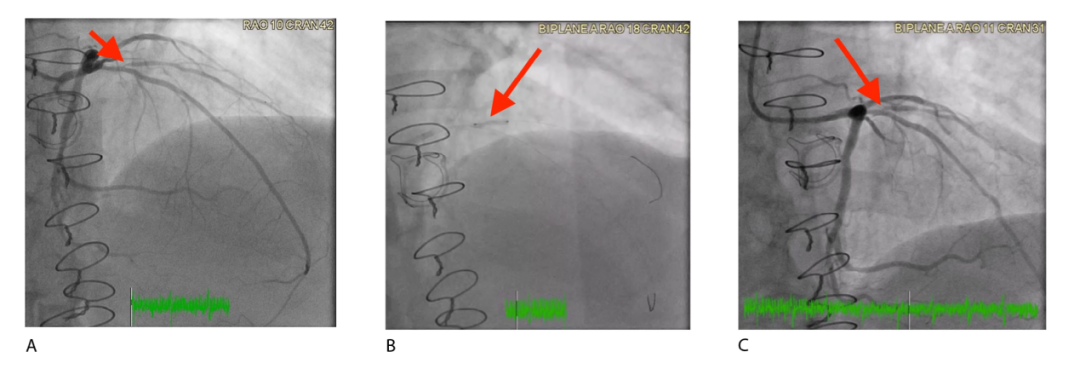

图3

注:(A)预处理图像显示受影响动脉中90%的ISR。(B)置入一个2.5×15mm的DCB,扩张至6个大气压,持续60秒。(C)治疗后图像显示,DCB介入后ISR完全消退,狭窄率为0%。